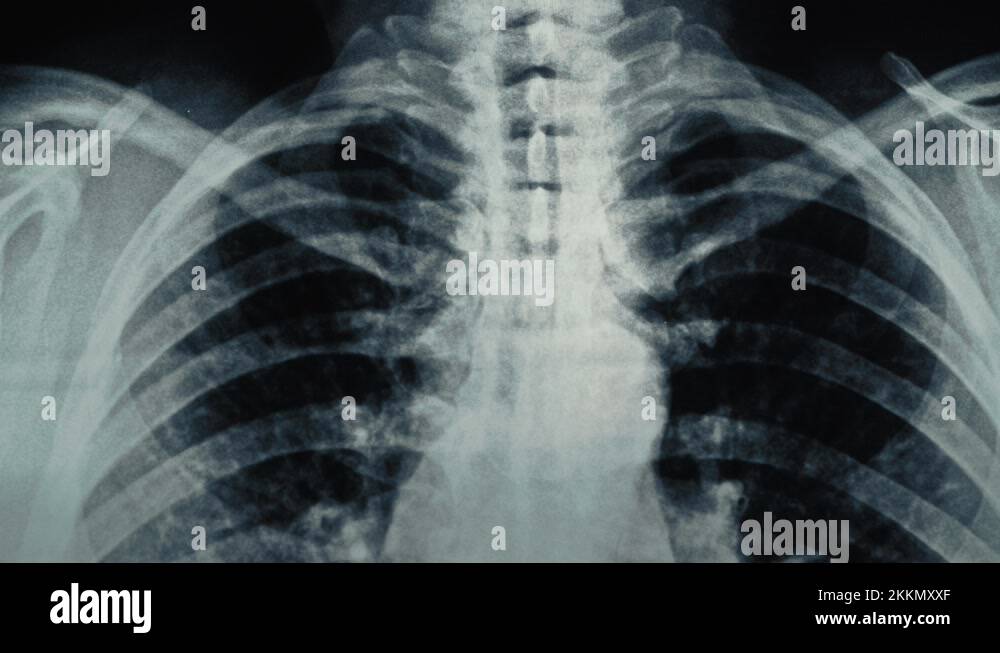

Would Asthma Show Up On A Chest X Ray . Instead, doctors may request lung function tests, which are tests that.  the majority of people with asthma will have a chest radiograph. Reported features of asthma include:   plain chest radiographs can be normal in up to 75% of patients with asthma.   chest radiography is the initial imaging evaluation in most individuals with symptoms of asthma. The value of chest radiography is in.